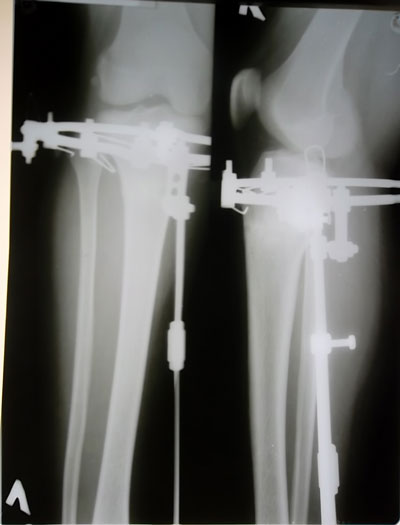

Дата операции 13.06.2013г.

Дата снятия аппаратов 10.09.2013г.

Срок лечения 88 дней.